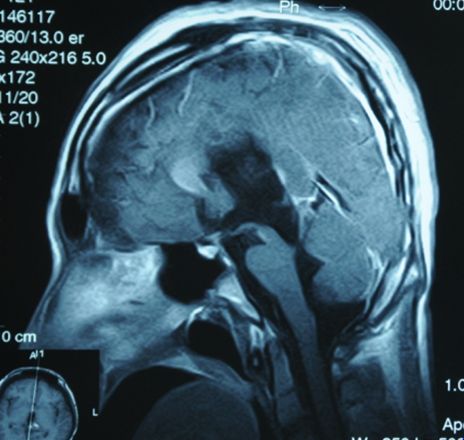

典型病例一:

手术前后